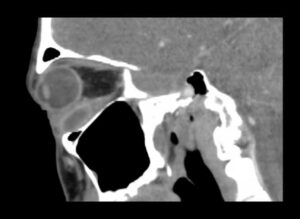

Inferior Rectus Abscess CT Sagital Unannotated. JETem 2025